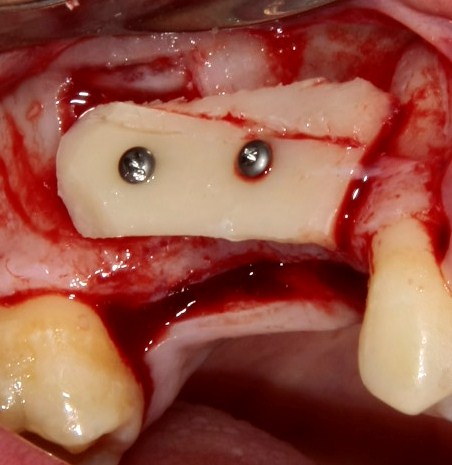

Вторая особенность — мы не адаптируем и не обрабатываем костный блок invitro, а фиксируем его так, как есть:

после чего обрабатываем — доводим до окончательной формы альвеолярного гребня:

Далее, можем приступить к установке имплантатов. Разумеется. по хирургическому шаблону:

Последняя картинка даёт представление о том, какой объем костной ткани мы «нарастили».

Поскольку принимающее ложе и аутокостный блок конгруэнтны, мы можем отказаться от использования барьерной мембраны. Она не нужна.